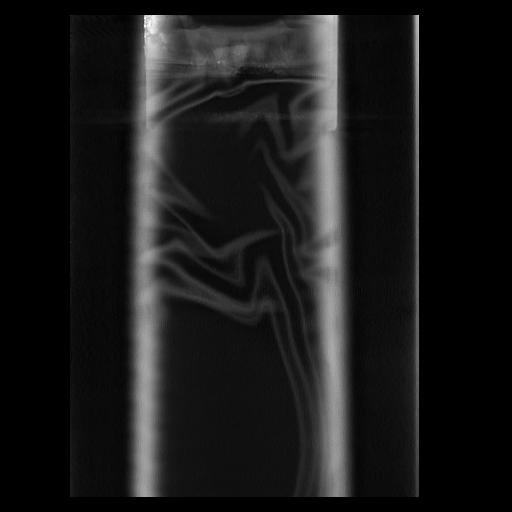

32 PULMON,CE,Coronal,3.000,PULMON,Coronal,